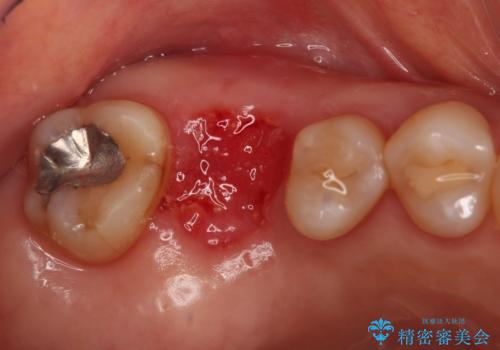

抜歯後そのままブリッジを入れるとブリッジと歯茎の間に大きなすき間ができてしまいます。その結果食べ物がつまりやすくなったり、息もれが生じたりと日常生活に支障をきたしてしまうことがあります。

抜歯後に骨を増やしてあげることで、ブリッジと歯茎との間にすき間が生じにくくなり、適合の良いブリッジを入れることが可能となります。